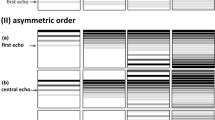

Partial Fourier (pF) is one method that can be utilized to decrease the length of the EPI echo train, and, therefore, shorten the TE, whilst maintaining a high spatial resolution [12, 13]. Partial Fourier exploits the Hermitian symmetry of k-space by acquiring all k-space lines in one half of k-space, and a reduced number of k-space lines in the other half [14]. However, motion that occurs during the diffusion encoding gradients can cause the k-space centre to shift away from the centre of the EPI readout [15, 16]. If the motion is large enough, then the k-space centre can shift completely out of the sampled region of k-space, causing severe signal loss in the reconstructed images. Motion can also cause a reduction in the effective resolution of the image if the k-space shift causes high k-space frequencies to not be acquired. Since pF reduces the acquired number of k-space lines, it is, therefore, more sensitive to motion induced phase error effects and must be used with care. Storey et al. [15] showed severe artefacts caused by rigid body motion in the brain which were reduced with an adaptive homodyne algorithm. Chang et al. [17] extended the use of an adaptive homodyne algorithm to multi-shot acquisitions in the brain. Zhang et al. [18] and Geng et al. [19] were able to correct for severe motion artefacts with motion compensated waveforms whilst using a pF factor of 0.75 in the liver and pancreas, respectively. Sources of motion artefacts in the liver and pancreas can be from cardiac pulsation and respiration. Van et al. [16] showed that phase correction can reduce motion induced worm like artefacts and signal loss in a homodyne reconstruction in the liver. Filli et al. [20] used a pF factor of 5/8 in the breast but did not report any considerable motion artefacts.

The multi-shot DWI acquisitions were based on the acquisition of a navigator echo for each shot, which was refocused from the imaging echo. The phase of the navigator was then used to correct for the phase variation between each shot during the reconstruction process in image space. Further details are given in [47]. All pF scans, both in-vivo and simulated, were reconstructed with a homodyne reconstruction [14]. Homodyne reconstruction restores only magnitude information, and the accompanied presented phase is the low resolution phase from the symmetrically sampled region [14].

To investigate the effect of pF on single-shot and multi-shot prostate DWI measurements, axial multi-slice free-breathing DWI scans were performed in all 10 healthy subjects with b-values of (100, 800) s/mm2 as recommended by the PI-RADS guidelines [9]. The scan parameters are shown in Table 1. Diffusion directions (− 0.5, − 1, − 1), (1, 0.5, − 1) and (1, − 1, 0.5) will from now on be referred to as dir 1, dir 2 and dir 3, respectively. The acquisition order was as follows (from inner to outer loop): slices, repetitions, shots, diffusion directions, b-values. However, it is motion during the diffusion encoding (which is of the order of 50 ms) that causes intravoxel dephasing and, therefore, signal loss.